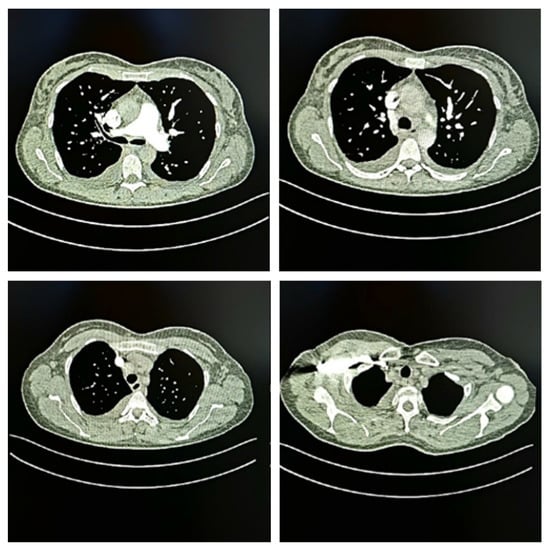

2. Case Description